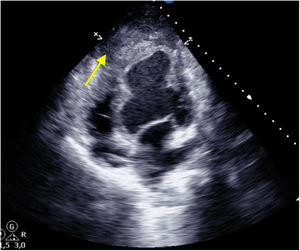

After 1 week on the urgent 0A waiting list, hemodynamic instability required an increase in pharmacological support, with transthoracic ultrasound revealing the rupture of the contained apical hematoma (Fig. 2, yellow arrow). Given the presence of refractory hemorrhagic shock despite measures, emergency surgery was scheduled to control the bleeding. However, coincidentally, a compatible organ became available for our patient, and a heart transplant was ultimately performed.